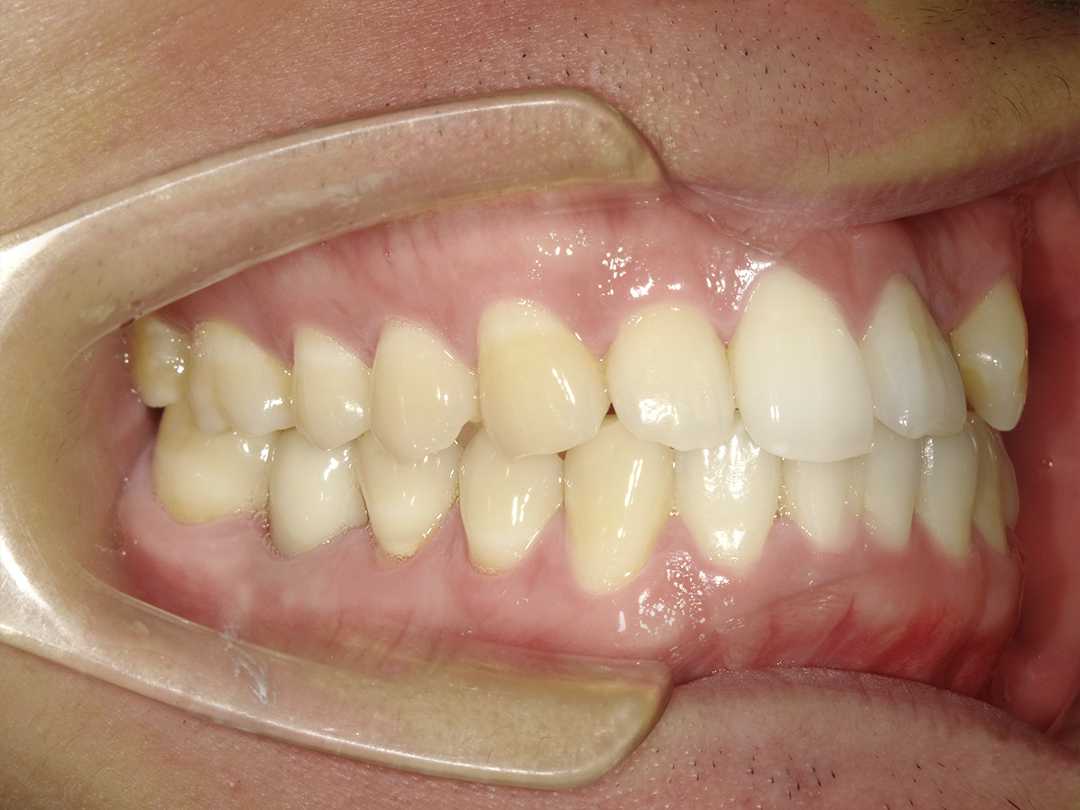

通過衛福部認證的專業技師,經由電腦設計及CADCAM數位先進製程,製作出堅固耐用、美觀自然的假牙。

美觀自然,提升生活品質與自信